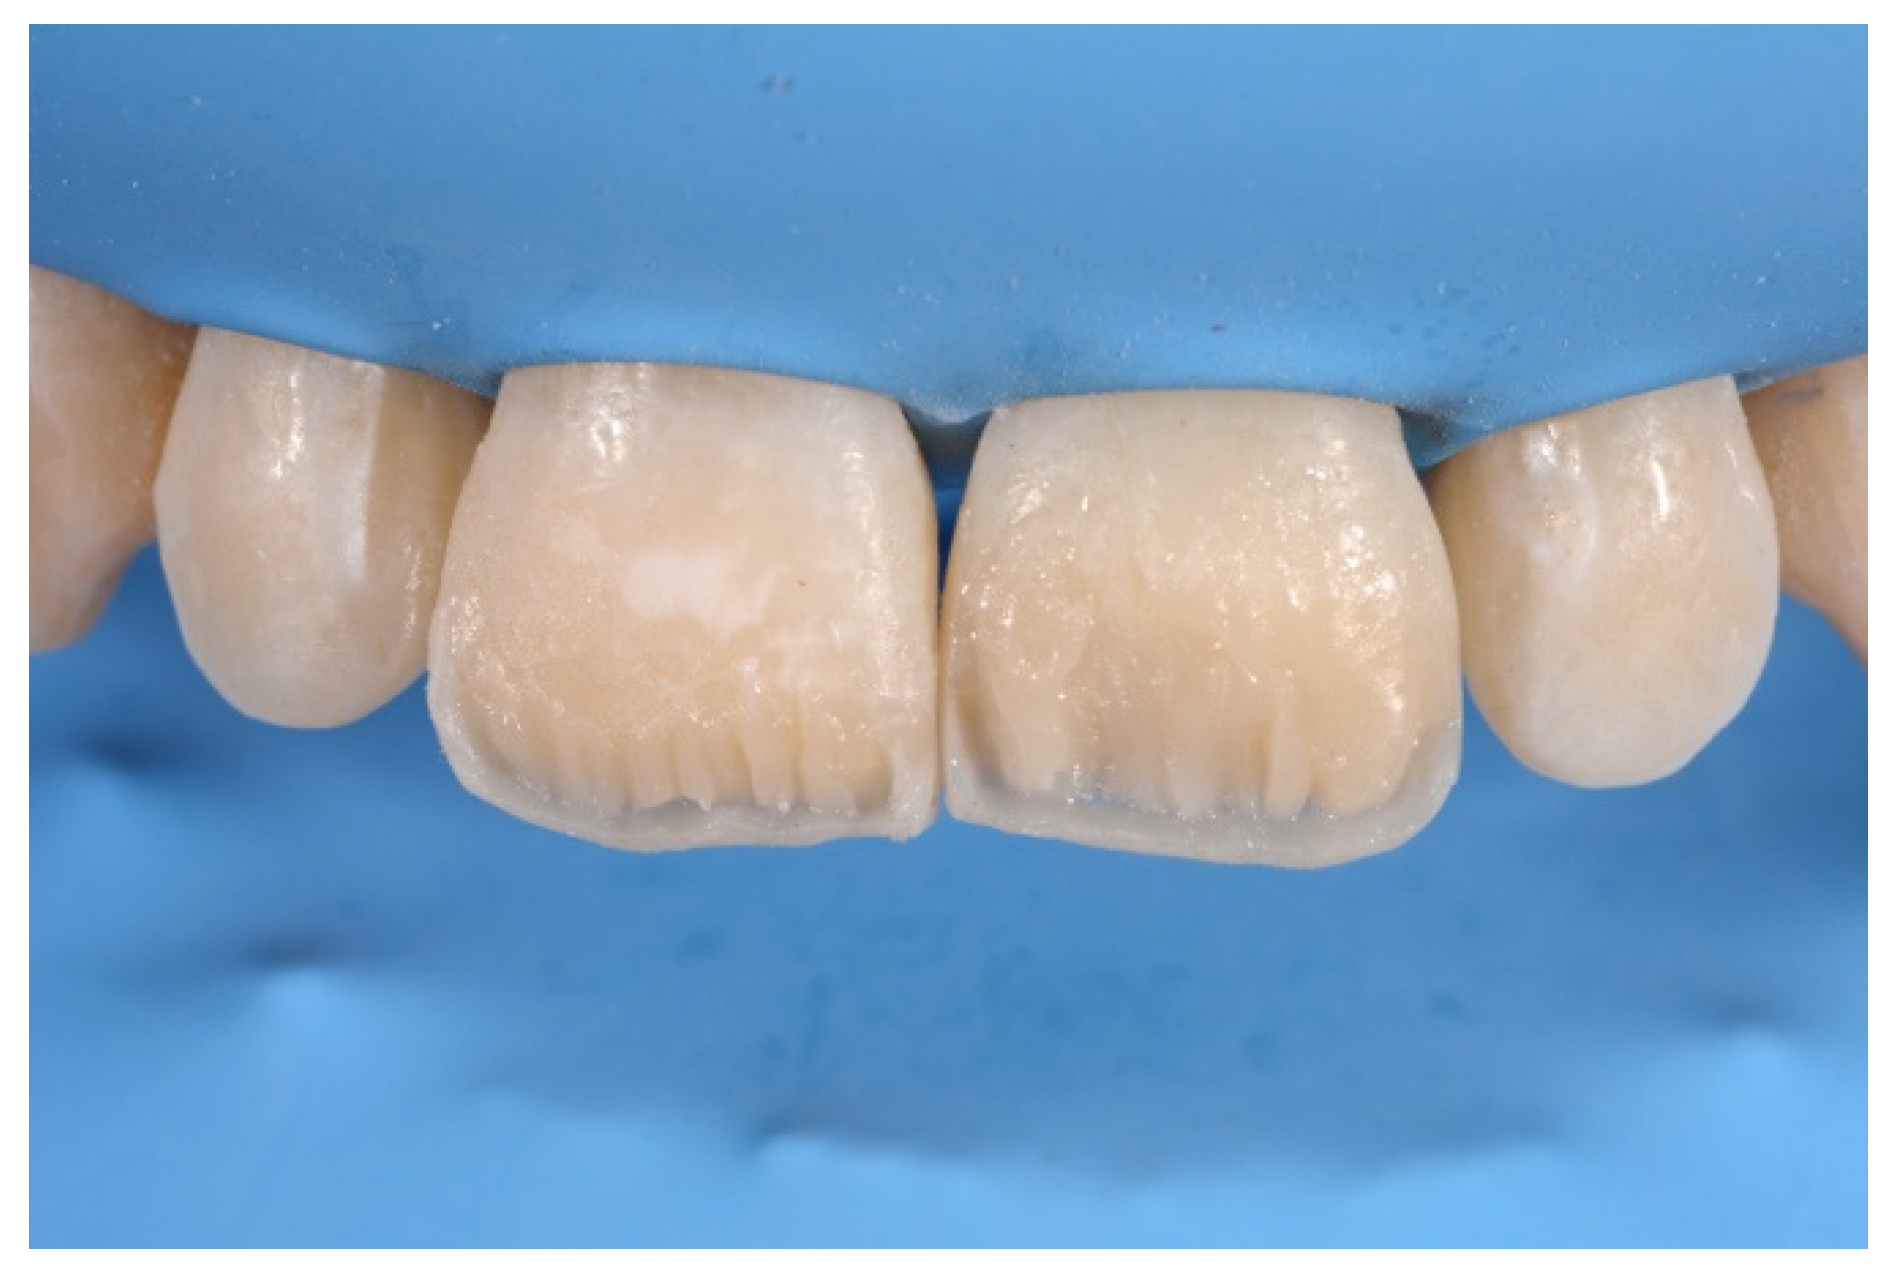

- Molding palatal wall and incisal margin;

- Building interproximal walls with matrices;

- Layering free-hand buccal surface.